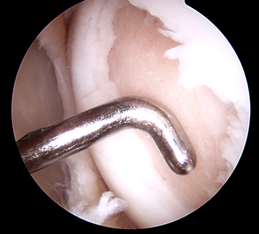

Step3:

Holes drilled in bone